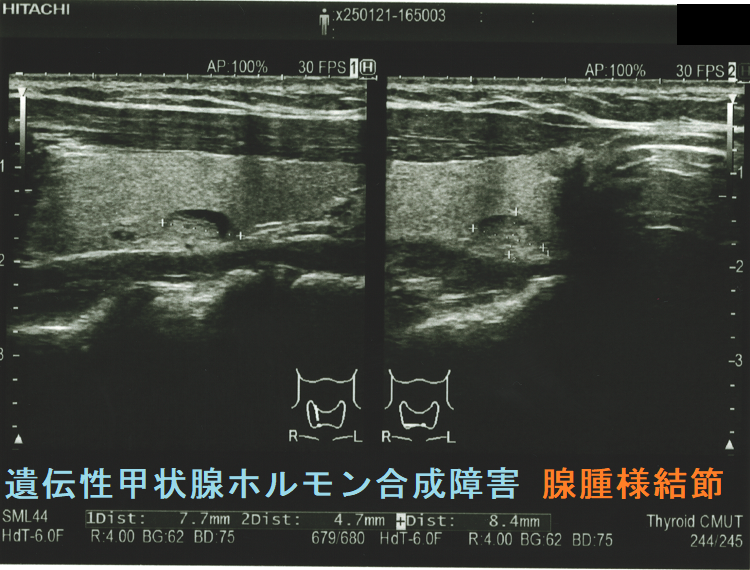

ケース③

遺伝性甲状腺ホルモン合成障害で、サイログロブリン異常症(サイログロブリン遺伝子異常症)以外は、血中サイログロブリンが上昇するにも関わらず、甲状腺自体の破壊性変化に乏しく、マシュマロ様の軟らかい腺腫様甲状腺腫の形態を取る事があります。

遺伝性甲状腺ホルモン合成障害の超音波(エコー)画像は色々なパターンがあります。

- 常染色体優性遺伝型;腺腫様甲状腺腫の形態になります。